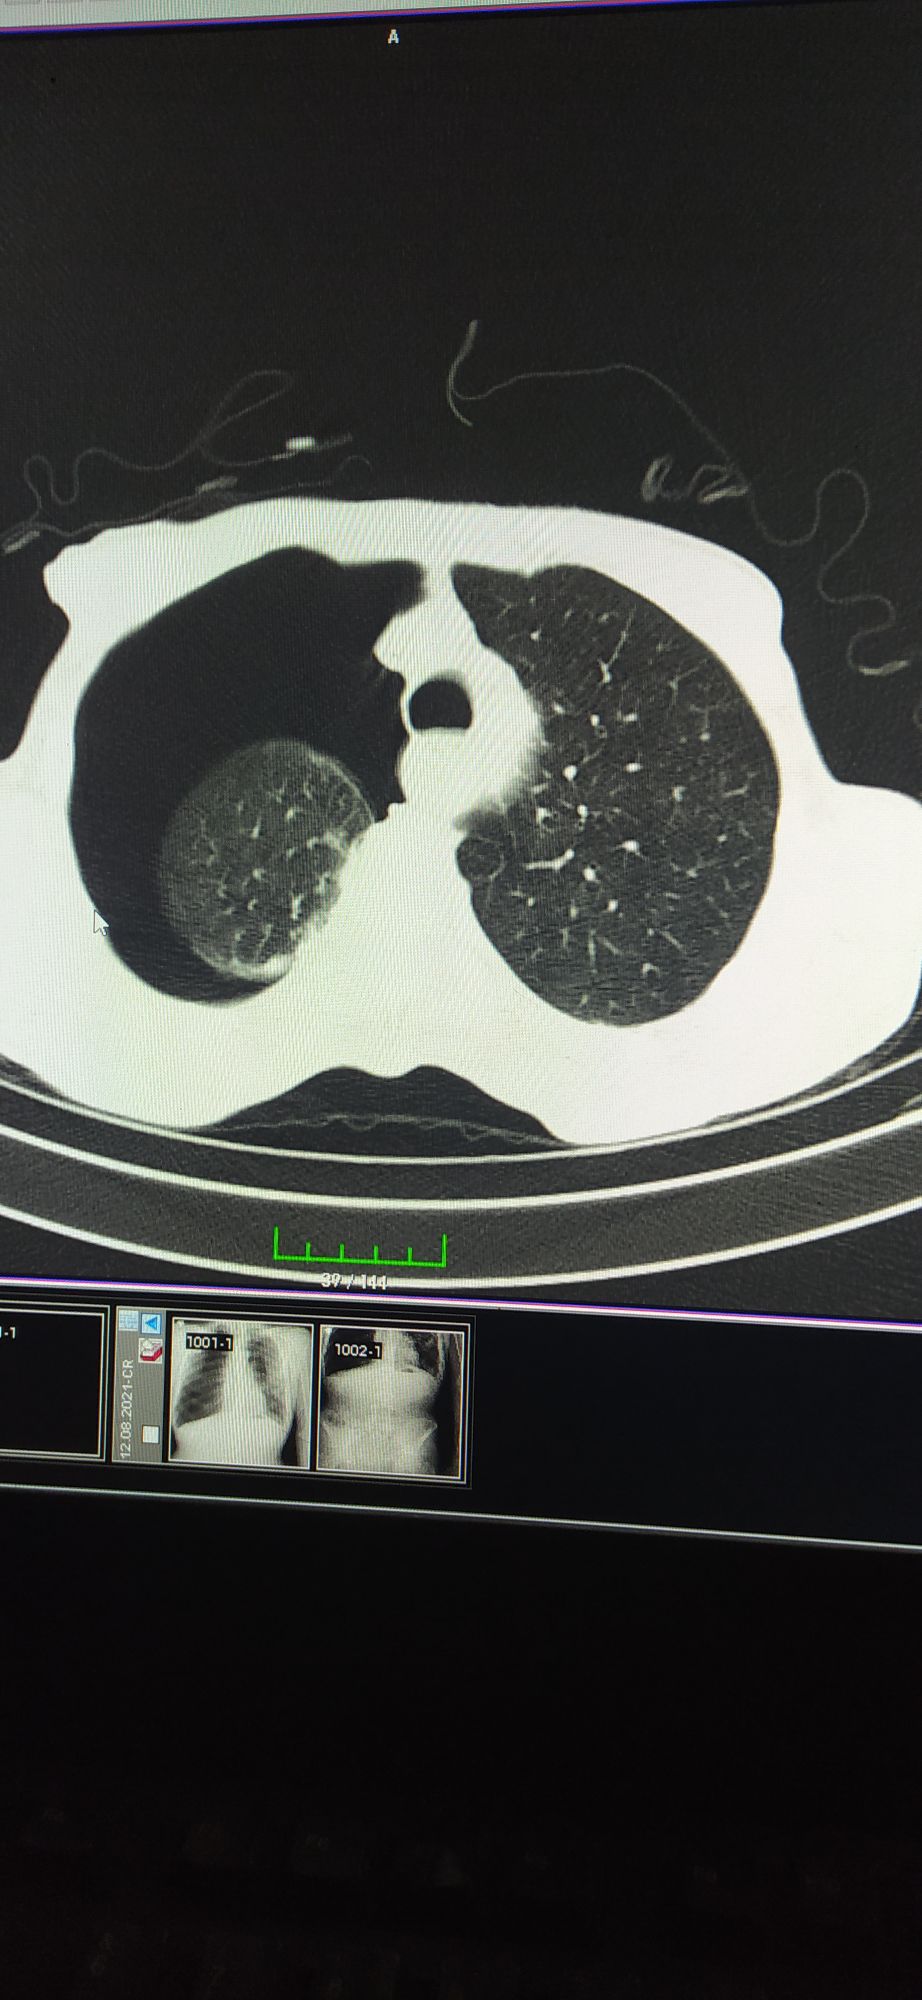

İatrogenic Pneumothorax

Pneumothorax

Central Catheter

Dispnea